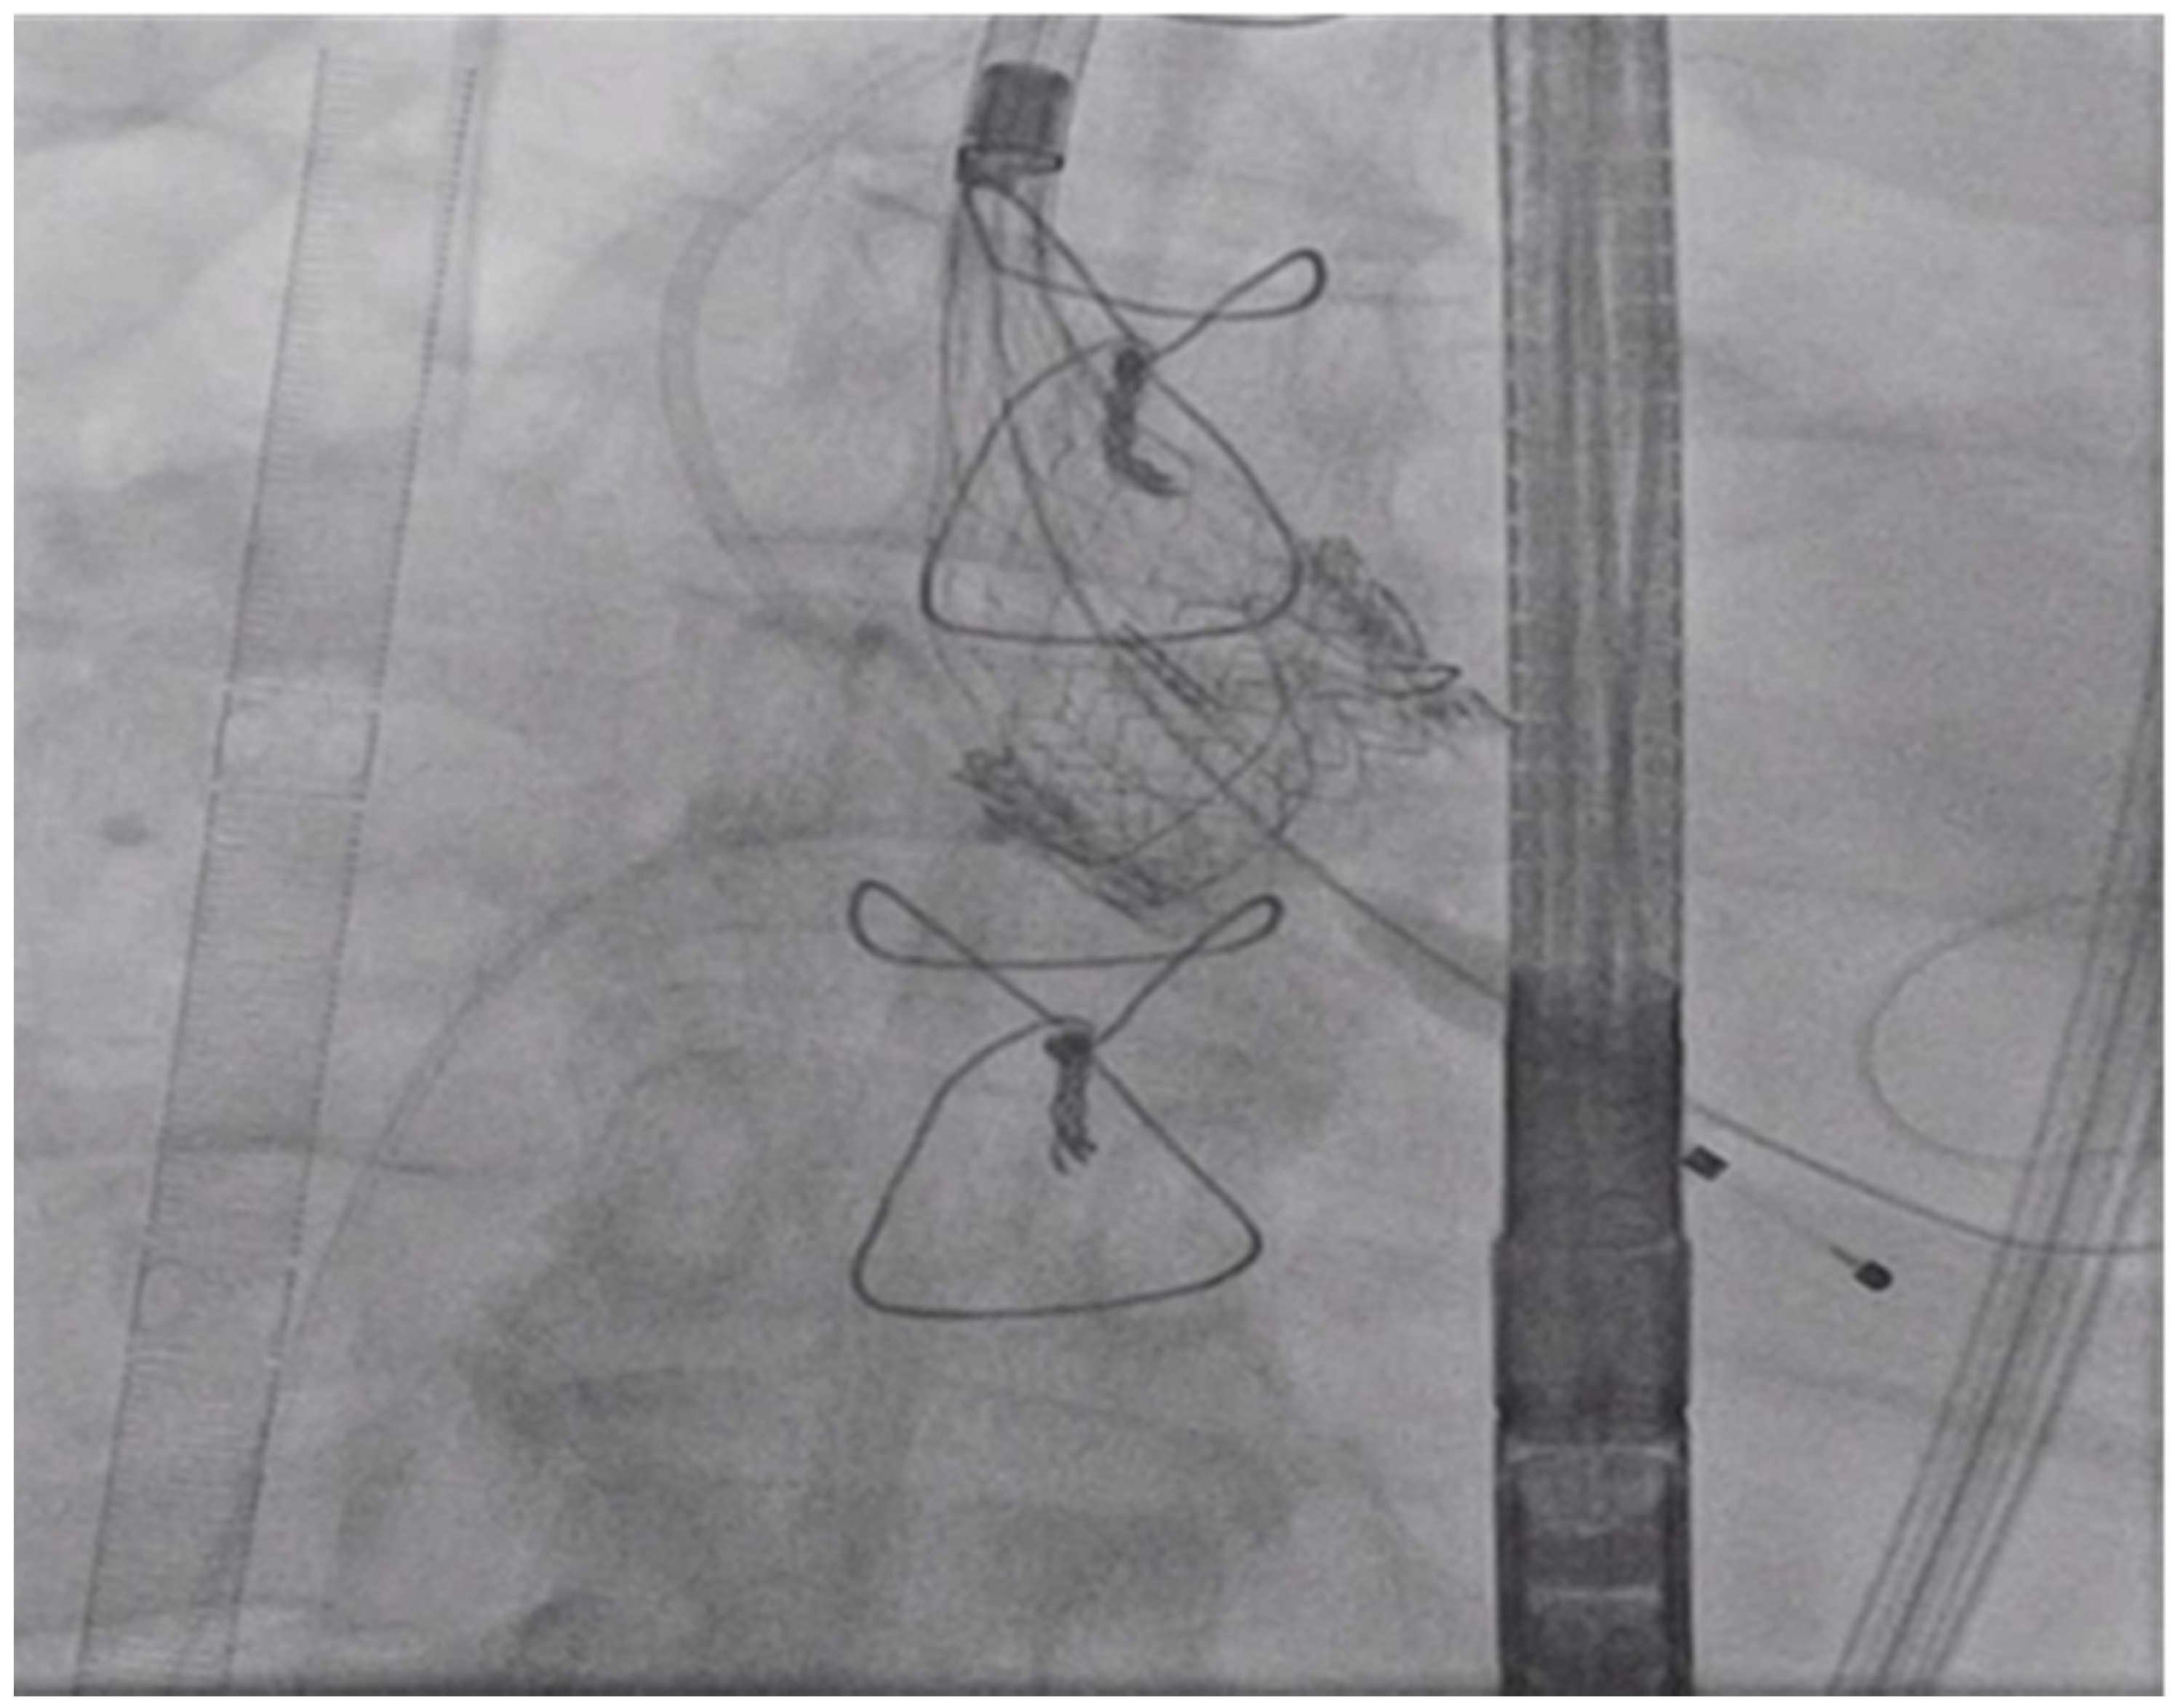

The CoreValve position was confirmed by TEE and fluoroscopy before its deployment. The rotational fluoroscopic view of is shown in Figure 5. TEE and aortogram showed a well-seated transcatheter aortic valve with trace perivalvular leak and good positioning of the prosthesis.

Figure 5.

Left Anterior Oblique (LAO) view: Valve is deployed.

The valve delivery catheter was removed from the wire and the 16 French Gore dry seal sheath was reinserted. A dual lumen pigtail catheter was placed into the left ventricle over the wire and hemodynamic measurements were obtained. The post procedural aortic valve mean gradient was noted to be 11 mmHg, and aortic regurgitation was mild with an index of 22% with trace paravalvular leak as shown in Figure 6.

Figure 6.

Trans-esophageal echocardiogram after valve deployment showing trace paravalvular leak.

The TandemLife® support was discontinued. The left common artery cannula was removed, and the Perclose sutures were tied. The right common femoral vein cannula and right common femoral artery sheath were removed, and the Perclose sutures were tied. The patient was transferred to the ICU in stable condition and was discharged two days after the procedure. At one month’s follow up, TTE showed a well-seated valve with no paravalvular leak and transvalvular mean gradient of 12 mmHg.